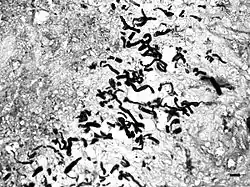

Pythium hyphae

In horses, subcutaneous pythiosis is the most common form and infection occurs through a wound while standing in water containing the pathogen.[3] The disease is also known as leeches, swamp cancer, and bursatti. Lesions are most commonly found on the lower limbs, abdomen, chest, and genitals. They are granulomatous and itchy, and may be ulcerated or fistulated. The lesions often contain yellow, firm masses of dead tissue known as kunkers.[4] It is possible with chronic infection, the disease can spread to underlying bone.[5]